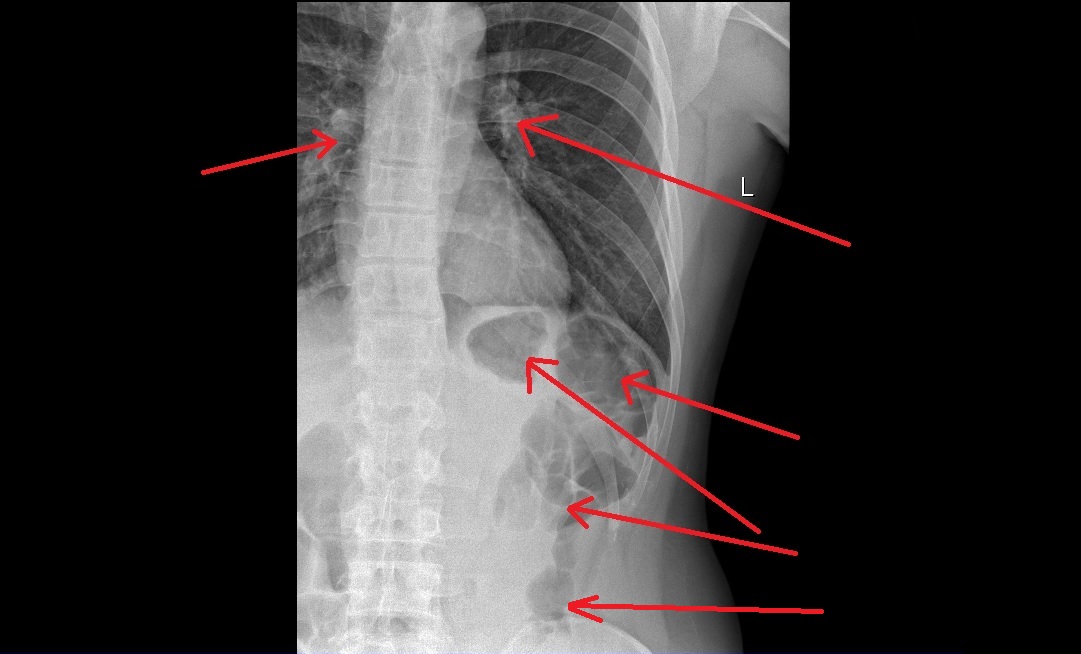

RTG hrudníka

@eduardo123 Haha.. To je hrubé črevo klasický obraz.Tlak na hrudi môže mať milión príčin. Úzkosti, stavy po Covide, fajčenie a zmeny na cievach... Atď...

tie flaky su pluca ak ich je vela je tam zapal. neviem s cim si siel k chirurgovi ale cvicenie ti neburovna chrbticu len nebudes mst bolesti

Bubliny sú črevá 😉Toto v pľúcach neviem.